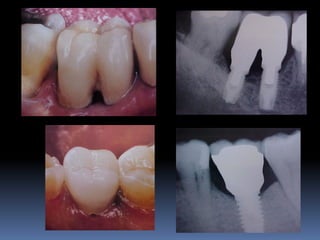

•Necessidades de reabilitações prévias

Dentística, periodontia, cirurgia, prótese, endodontia , ortodontia e DTMs

•Áreas de interesse implantar

Perdas dentárias , tecido ósseo e tecido mucoso